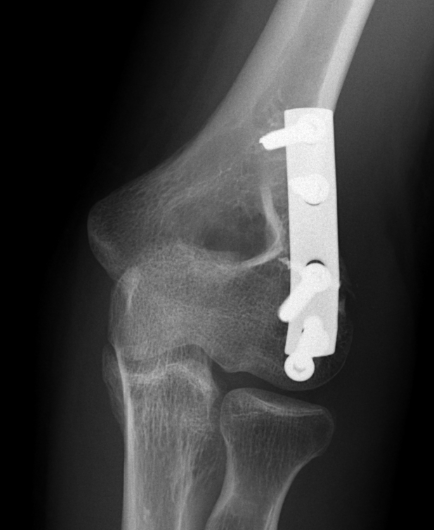

Lateral approach and ORIF

Technique

Arm on side table with tourniquet

- lateral approach centered on lateral epicondyle

- split extensor muscle

- open capsule and identify capitellum fracture

- reduce fracture

Usually AP headless compression screws (violates articular surface)

- +/- PA screws (risk AVN)

- +/- excise isolated cartilage lesions

- +/- postero-lateral plate

ORIF with AP screws

ORIF with PA screws and posterolateral plate

Large capitellum fracture / lateral column ORIF with plate and screws